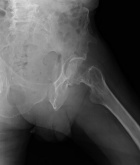

67 year old male with c/o L hip pain for one month presents with sudden severe increase in pain and inability to bear weight.